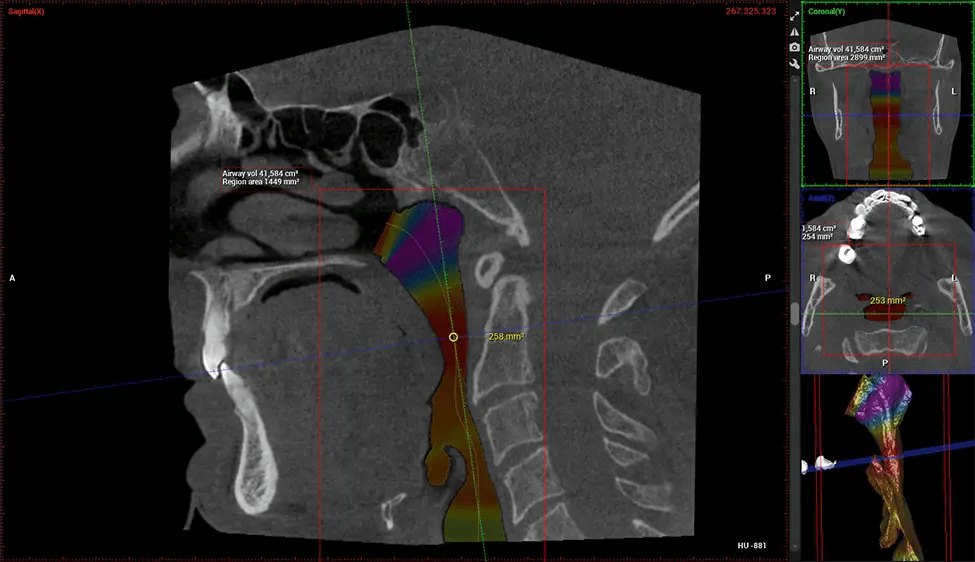

Cone Beam Computed Tomography (CBCT) is an advanced imaging technique used in dentistry and maxillofacial surgery to obtain detailed 3D images of the oral and maxillofacial structures. At Dr G Dental Studio, our CBCT scanners utilize a cone-shaped X-ray beam and a specialized detector to capture images from different angles. A computer then combines these images to create a 3D representation of the patient’s oral anatomy.

This 3D scan, called cone beam computed tomography, gives your dentist a more complete image of your oral anatomy and disease processes than a traditional X-ray. Unlike conventional X-rays, which capture a 2D image of your mouth from various angles, a 3D scan takes multiple digital X-rays for one image. It provides a complete view of your jaw, teeth, nerves, and soft tissues. This enhanced view allows dentists to detect minor issues not visible in traditional 2D scans, such as impacted wisdom teeth or bone fractures in the sinus cavity.

There are many benefits to using CBCT technology, especially compared to the traditional 2D X-ray format. One of the most significant advantages of CBCT scans is that they provide much more information than traditional X-rays. A scan lets your dentist see images from all angles of your jaw and mouth, including your sinuses, nasal cavity, cheekbones, and other surrounding areas. This added information helps your dentist craft a comprehensive treatment plan that addresses all aspects of your oral health.

Another significant benefit is that 3D imaging provides more precise images of your bone structure. These images are more detailed, providing you with a more accurate diagnosis. An accurate diagnosis means better treatment for you.

The patient is first positioned in the CBCT scanner, which typically consists of a rotating arm that houses the X-ray source and a detector. The patient’s head is immobilized to ensure accurate image capture. The X-ray source and detector rotate around the patient’s head, capturing various X-ray images from multiple angles. As the X-ray source rotates, it emits the cone-shaped X-ray beam towards the detector. The detector captures the X-ray images, which are then processed by the CBCT software.

After the scanning process, the captured X-ray images are processed by the CBCT software, which applies algorithms to reconstruct a detailed 3D image of the scanned area. The software compiles these individual X-ray images and creates a digital 3D representation of the patient’s anatomy. The reconstructed 3D CBCT image can be viewed and analyzed by the dentist or radiologist. This image can be manipulated, rotated, and zoomed in or out to examine specific structures and evaluate the patient’s condition.